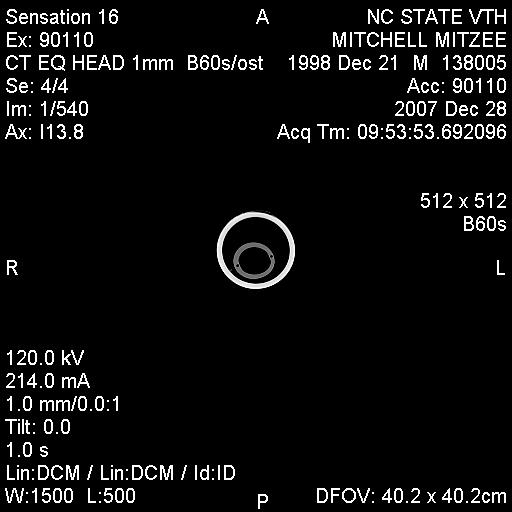

Posted on Sunday, Jun 24, 2007 - 3:39 pm: Greetings Everyone,I have finally received some of Mitzee's xrays, though it appears that I'm missing several... hmmm... Anyway, I thought I would give everyone an update. After two weeks of inpatient care (IV antibiotics, anti-inflamatory agents, a few different wound site I&Ds, several xrays and another fistulogram, etc...), she was discharged on 6/7/7. The final fistulogram showed NO evidence that the draining sinus tract communicated with the adjacent tooth root (4th premolar), but, rather, seemed to travel to the empty alveolar socket of her previous surgical site (the removed 3rd premolar). I had decided I did not want to attempt to manage her on my own, so I arranged to board her and Rorie at a facility owned by an equine vet, kind of like a lay up hospital situation... She's been getting daily assessment and care of her wound, the barn has a great fly control system and, so far, she usually goes out at night and stays in during the hot day. Plus, when she and Rorie are out, they're with other mare/foal pairs and that's a nice bonus for Rorie. Mitzee's eating well, her weight is good, and her activity is normal. And, though tissue healing is occurring, significant swelling of her left submandibular area persists and there are two remaining tracts that drain purulent material, though it is less than previously observed. I have decided to see how things go for awhile and "embrace" this conservative approach... clearly, the surgeon was not interested in pursuing more surgery at the time of her discharge, though when I corresponded with him recently (and showed the same pictures I am posting below) he suggested we get a CT scan. Of course, a CT scan appears to require general anesthesia and I would have to take her to a larger referral, probably academic, center. Based on where I am in VA, the closest facilities are NC State in Raleigh, NC, Marion duPont Scott in Leesburg, VA, or VA Tech in Blacksburg, VA... I do still worry that there's something "left behind" in the wound, perhaps a necrotic bone fragment???, that is continuing to feed this low level infection... At this point in time, she is almost 6 weeks postop from her initial surgery to remove premolar #3... Rorie was 8 weeks old last Tuesday... What does everyone think???? Thanks! Martha

Posted on Sunday, Jun 24, 2007 - 7:09 pm: I presume the folks who look at the original and complete set of radiographs, see no dead bone? Martha, considering everything, the swelling itself is not a bad sign and may take time to resolve. The radiograph is difficult to evaluate as it seems to lack much detail, possibly a problem with the generalized swelling. The parts we can make out look ok. Most important their is still purulent drainage, indicating the bodies attempt to rid itself of infection and/or necrotic material. As long as it is improving the conservative approach may work.DrO |

Posted on Sunday, Jun 24, 2007 - 8:57 pm: Thanks Dr. O and Everyone,Sorry, I know the film is somewhat poor... the surgeon's office girl sent me several films via an email attachment, so I wonder if when I downloaded them and reduced their sizes maybe I lost some resolution??? Hopefully, I will get a CD of all these films and can post better copies for your review... The surgeon reviewed all the films with me on the day of Mitzee's discharge and he felt pretty comfortable with everything being O.K. at that time, but, recently, when he saw the pictures I posted above, he suggested we get a CT scan... Dr. O, what's your take on that???... and, BTW, since you're in NC have you had "experiences" with NC State's vet school??? They're only down I-95/I-85 about 120 miles or so from Richmond and it would be a manageable trip to make, if needed... Regarding the issue I raised previously about hyperbaric oxygen therapy, I did talk to UT Knoxville and found out that their old chamber (a portable one) is not operational now in order to be replaced with an upgraded chamber (one that is permanently in place), hopefully sometime by the end of July... So, if there's ongoing evidence of infection, I still want to keep HBOT in mind... Thanks! Martha |

Posted on Monday, Jun 25, 2007 - 1:39 am: The picture quality IS poor, but it almost looks like there is some healing going on. |

Posted on Thursday, Dec 27, 2007 - 10:48 pm: Hey HA friends,Just wanted to say that Mitzee and I have arrived in the Tarheel state tonight! In a nutshell, for the past several months, Mitzee has continued to have intermittent serosanguinous vs. scant purulent drainage from her submandibular area and a significant ?fibrosed deformity of her jaw, though really no other indications of clinical problems... she's chewing well, weight is good, afebrile, etc... Sometime back in the summer, our equine surgeon had suggested that we undergo a CT scan (you guys may remember that even though Mitzee had significant purulence and edema following her initial surgery in May, the surgeon was very reluctant to "re-explore" the area due to the difficulty of that first surgery and the lack of evidence from her contrast fistulograms that the adjacent tooth root was involved in any infection)... So, though I had hoped to have her undergo this in the summer, NC State's Vet School was awaiting a "functional" table to use for equines in the scanner; and, though I was considering going to VA Tech instead, I had that little foot fracture in July which pretty much impaired my equine activities for several months. Given that she looked so good clinically, I decided to wait for NC State's table to be operational, but also given the continued appearance of the submandibular drainage, I still wanted to rule out any retained ?necrotic bone fragment or area of osteomyelitis in her mandible. So, tomorrow is the big day for the CT scan. The CT scan findings will direct any subsequent care, more surgery vs. medical therapy vs. nothing needed... I hope to get the CT films and post those sometime this weekend... wish us luck! Martha P.S. And, BTW, the other really wonderful thing is that I weaned baby Rory about a month ago (I changed the spelling of his name when I submitted his registration papers)... and in doing so, I moved Mitzee to another facility; well, I've spent alot of time with her over the past month and we have actually started to bond; she clearly has begun to trust humans and, in particular, me! Just the fact that I can groom her completely, touch every area of her face/head, even the submandibular area without too much protest, pick up her hooves (briefly) is all really wonderful! The new barn where I'm boarding her is a very busy hunter/jumper/eventing barn that gives a huge number of lessons, primarily to kids; Mitzee has really gotten desensitized to all the chaos that goes on and all the little girls at the barn just love her (she is the only Appaloosa there and her "rescue" history has made her interesting to everyone there)... I have really begun to marvel at the smarts this mare has and how willing she is to tolerate many different situations; I really believe that she will be under saddle in the next several months and that she will make a wonderful and safe mount! |

Posted on Saturday, Dec 29, 2007 - 9:43 am: Thanks for the update Martha and am surprised to hear you are having problems. The lack of problems on the last radiograph suggest this should have healed in most cases. There are two explanations:1) a foreign body, possibly a dead piece of bone 2) a resistant infection either bacterial or fungal Hopefully the CT scan will help better define the problem so it can be fixed but surgery with thorough debridement and good microbial work up are likely to be required whatever they find. Keep us appraised Martha. DrO |

Posted on Saturday, Dec 29, 2007 - 8:14 pm: Well, thanks for everyone's comments!Here's the scoop... the CT clearly showed infectious "involvement" of the adjacent tooth (left lower 4th premolar), though fortunately, the root and the pulp appeared to still be healthy; also, an area of the mandible inferior to the previously removed tooth (left lower 3rd premolar) had a "sequestrum", sort of under the now empty alveolar socket, which is well healed. So, immediately following the CT, after the surgeon reviewed it with the radiologist, Mitzee got moved to the OR (still under general anesthesia) and debridement of the affected areas began. Once the surgeon performed an oral exam, he was also able to demonstrate an orocutaneous fistula, corresponding to the exact area on her lateral jaw where she has had continued intermittent drainage for the past several months. The surgery and anesthesia were uneventful and she looked great when I left her last night (I'm on call today at work)... I will probably be able to pick her up as early as tomorrow, but that will depend on how much sleep I get tonight. Hopefully, I will be able to post some pictures of her xrays and CT scan for everyone to see... NC State has this great program, called Amicus, that "converts" the two dimensional information from the CT scan into three dimensional, COLOR, pictures and WOW, what information they reveal... just remarkable (I doubt I will be able to post any of those pictures due to the licensing issues with the software company)... Also, the veterinarians and staff of NC State have been AWESOME... I'll try to post pictures tomorrow... Martha |

Posted on Tuesday, Jan 1, 2008 - 11:08 pm: Hey Everyone,Sorry for the delay in posting the images... Mitzee was discharged on Sunday (POD 2) and I DrOve down to NC, picked her up, and travelled back to VA in the worst pouring down rain (not complaining, we still do have DrOught conditions a bit...) Anyway, I was on call the next day (New Years eve) and had a killer night, so I am still kinda brain dead today... I've managed to crash my laptop several times with the disc I was given at NC State... just wondering if it has anything to do with my new laptop OS, Vista, but now, finally, I've managed to load some of the study pictures onto my old laptop (hopefully the keyboard won't quit like it did this summer). The plain xray is not great... possibly me altering it in the download process??? Anyway, it is a lateral so you see both sides of the jaw and you have to focus on the near structures (the left side), not the far ones (the right side); basically, it shows distortion of the the left lower premolar #2, which has occurred following removal of #3 last May, and compensatory changes in the left upper arcade (see the big ramp/points above). The few CT views I've uploaded show extensive bony proliferation and periosteal reaction of the left hemimandible, an absent left lower 3rd premolar tooth, as well as some radioopaque densities below this area, presumed to be ?tooth fragments or cement debris following the previous surgery; there is one particular linear density located in the center of this area that was felt to represent a possible "sequestrum" and was removed... also, you can see a radiolucent tract that exits the lower portion of the left hemimandible below the empty alveolar area of the absent 3rd premolar. A lytic lesion is seen associated with the lateral aspect of left lower 4th premolar near the gingival margin and another draining tract travels between this front/rostral portion of the left lower 4th premolar tooth and the lateral aspect of the mandible; my discharge papers state that the CT findings "are consistent with peridontal abscessation and a draining tract", however the surgeon believes the root and pulp of the left lower 4th premolar tooth are still healthy, so we may have a ?50/50 chance of saving that tooth. I have also attached a few other pictures of Mitzee undergoing her CT scan under general anesthesia, her recovery from GA, and a view of the her face following the surgery where the diseased areas were debrided. Her discharge papers note the final diagnosis as "chronic osteomyelitis of the left mandible and peridontal disease adjacent to left mandibular premolar tooth #4". I'll keep everyone posted on her recovery. Thanks!!! Martha

Posted on Monday, Jan 7, 2008 - 4:56 pm: O.K., I am going to try and load the CT images again... please refer to my descriptions of them above. Also, the surgeon from NC State called me today and reported the results of the cultures taken during surgery; Mitzee has grown two types of anaerobic, gram negative rod bacteria, a Prevotella "species" and Fusobacterium nucleatum. He said that he had not had a Prevotella isolated from equines in the past, but that the Fusobacterium is a common oral bacteria in a number of species.... Now, the plan had been for Mitzee to receive two weeks of postop antibiotics, trimethoprim/sulfamethoxazole (Bactrim DS) and when I brought her home on POD#2, I was able to give her the PM dose by syringing paste directly into her mouth (she did protest a little); for the next 24 hours, I was on call and during my absence the barn staff failed miserably in getting any drug into her! I certainly didn't want any of the barn staff to sustain injuries, nor did I want Mitzee to be hurt (apparently, she got into her rearing mode...), so I spoke with the surgeon then and he said I could forego her oral antibiotics (afterall, the surgical debridement was the "definitive" therapy!). Today, he mentioned that metronidazole (Flagyl) was the typical antibiotic for anaerobes, but that horses tolerate it even less than the Bactrim she had been on... so, since he felt good about the debridement, we are not treating her with antibiotics. The plan is to (as long as she looks good "clinically") take her back to Raleigh in about 4 weeks so he can examine her oropharynx and HOPEFULLY see that her orocutaneous fistula is HEALED and that the left lower premolar #4 is still O.K.!!! I'll keep everyone posted!Martha P.S. Keep in mind, when looking at the scans below, you are looking at a "cross-section" or axial image of the head, UPSIDE down... remember that she was laying on her backside to undergo the scan... also, the right side of the image is Mitzee's left side... notice the dramatic difference between the two sides, i.e., each hemimandible...

| Moderator: DrO |

Posted on Tuesday, Jan 8, 2008 - 8:07 am: They really caught the fistula and infected mandible well. Good luck with the surgery outcome Martha.DrO |